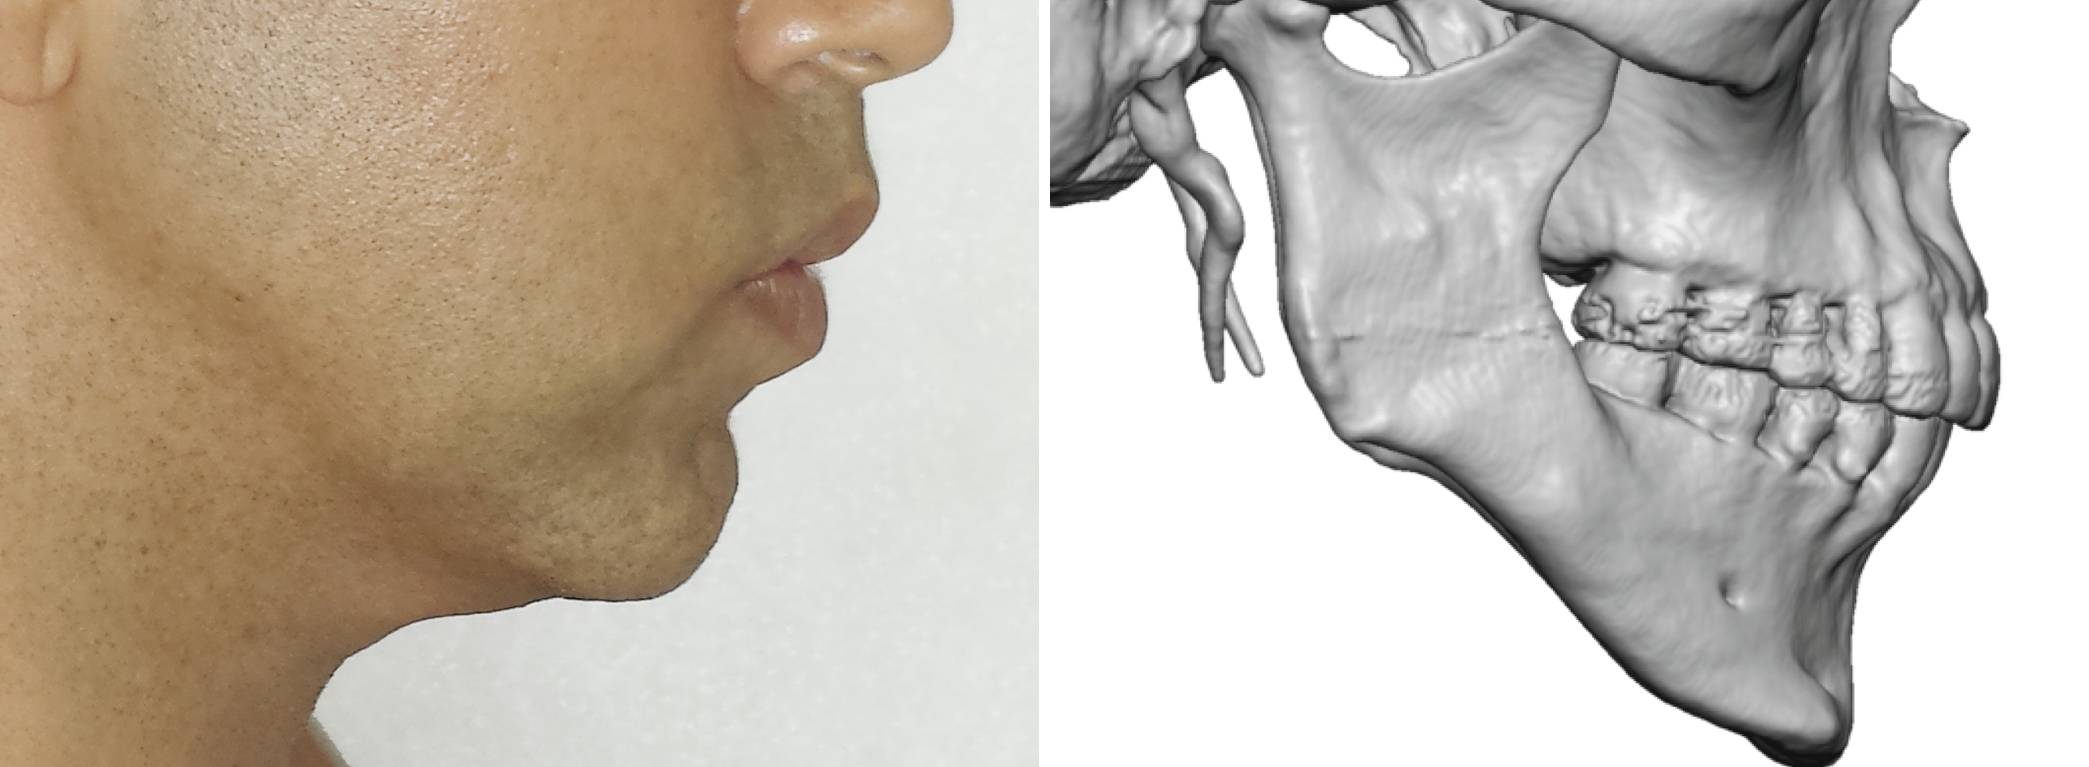

Hypothetically would a nicotine + ashwaganda be used as a poor man’s AI and delay of growth plate closure? We all know nicotine activates the liver enzymes that breakdown estrogen and reduces aromatese thus stops test turning into estrogen and gets rid of it + ashwaganda lowering cortisol. Those 2 things = growth plate closure? Anyone know if this is stupid or not? (Note im 20 and still in puberty and have mistakenly done both theese things just because I wanted to but didn’t know it could potentially benefit? Im also a late bloomer so could be that)